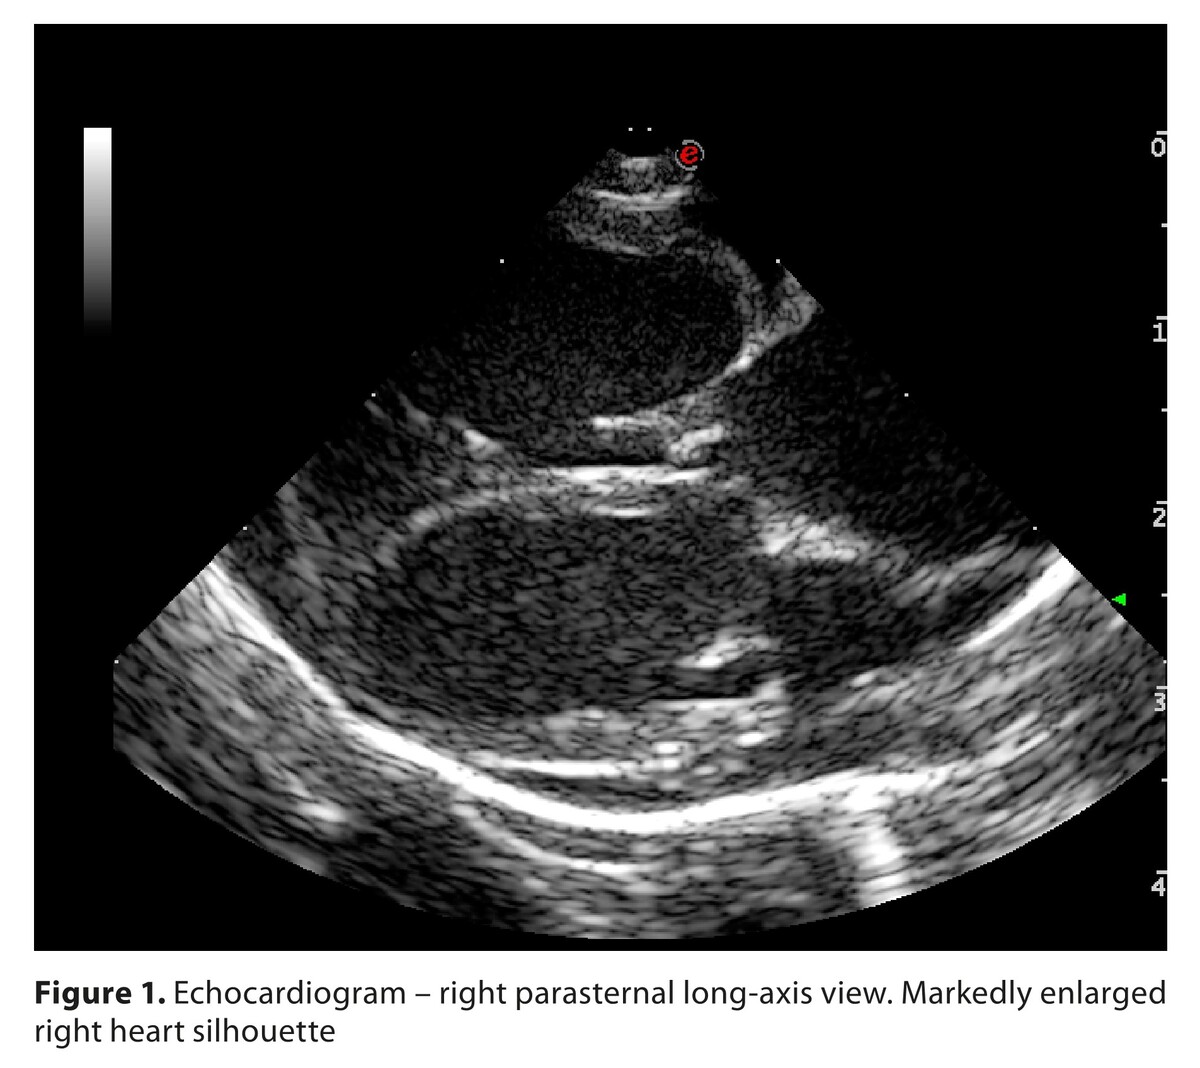

Dirofilaria immitis is an emerging parasitic threat in Central Europe with veterinary and zoonotic relevance. The case is described of a fatal autochthonous case in a seven-year-old Cavalier King Charles Spaniel from south-eastern Poland, with no travel history. The dog presented with dyspnea, ascites, cough, syncope, and cyanosis; echocardiography revealed right heart enlargement, tricuspid regurgitation, pulmonary hypertension, and left ventricular diastolic collapse. Euthanasia was performed due to poor prognosis. Necropsy identified six pre-adult worms in the right atrium, ventricle, and pulmonary outflow tract, with pulmonary congestion and oedema. This prepatent infection confirms local transmission of D. immitis in Poland and highlights the growing risk of autochthonous dirofilariosis in Central Europe, driven by climate change, vector spread, and animal movement. Vigilance is warranted given the public health implications and potential for misdiagnosis of human pulmonary lesions.